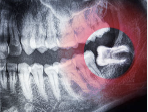

3. 사랑니 주위염 – 입 안 깊은 곳 잇몸이 붓는 경우

- 사랑니가 완전히 나지 않거나 부분 매복된 경우, 주변 잇몸에 세균·음식물 쌓이며 염증 유발

- 잇몸이 국소적으로 붓고, 입 벌리거나 음식을 씹을 때 통증

- 발열이나 턱 통증까지 동반되기도 함